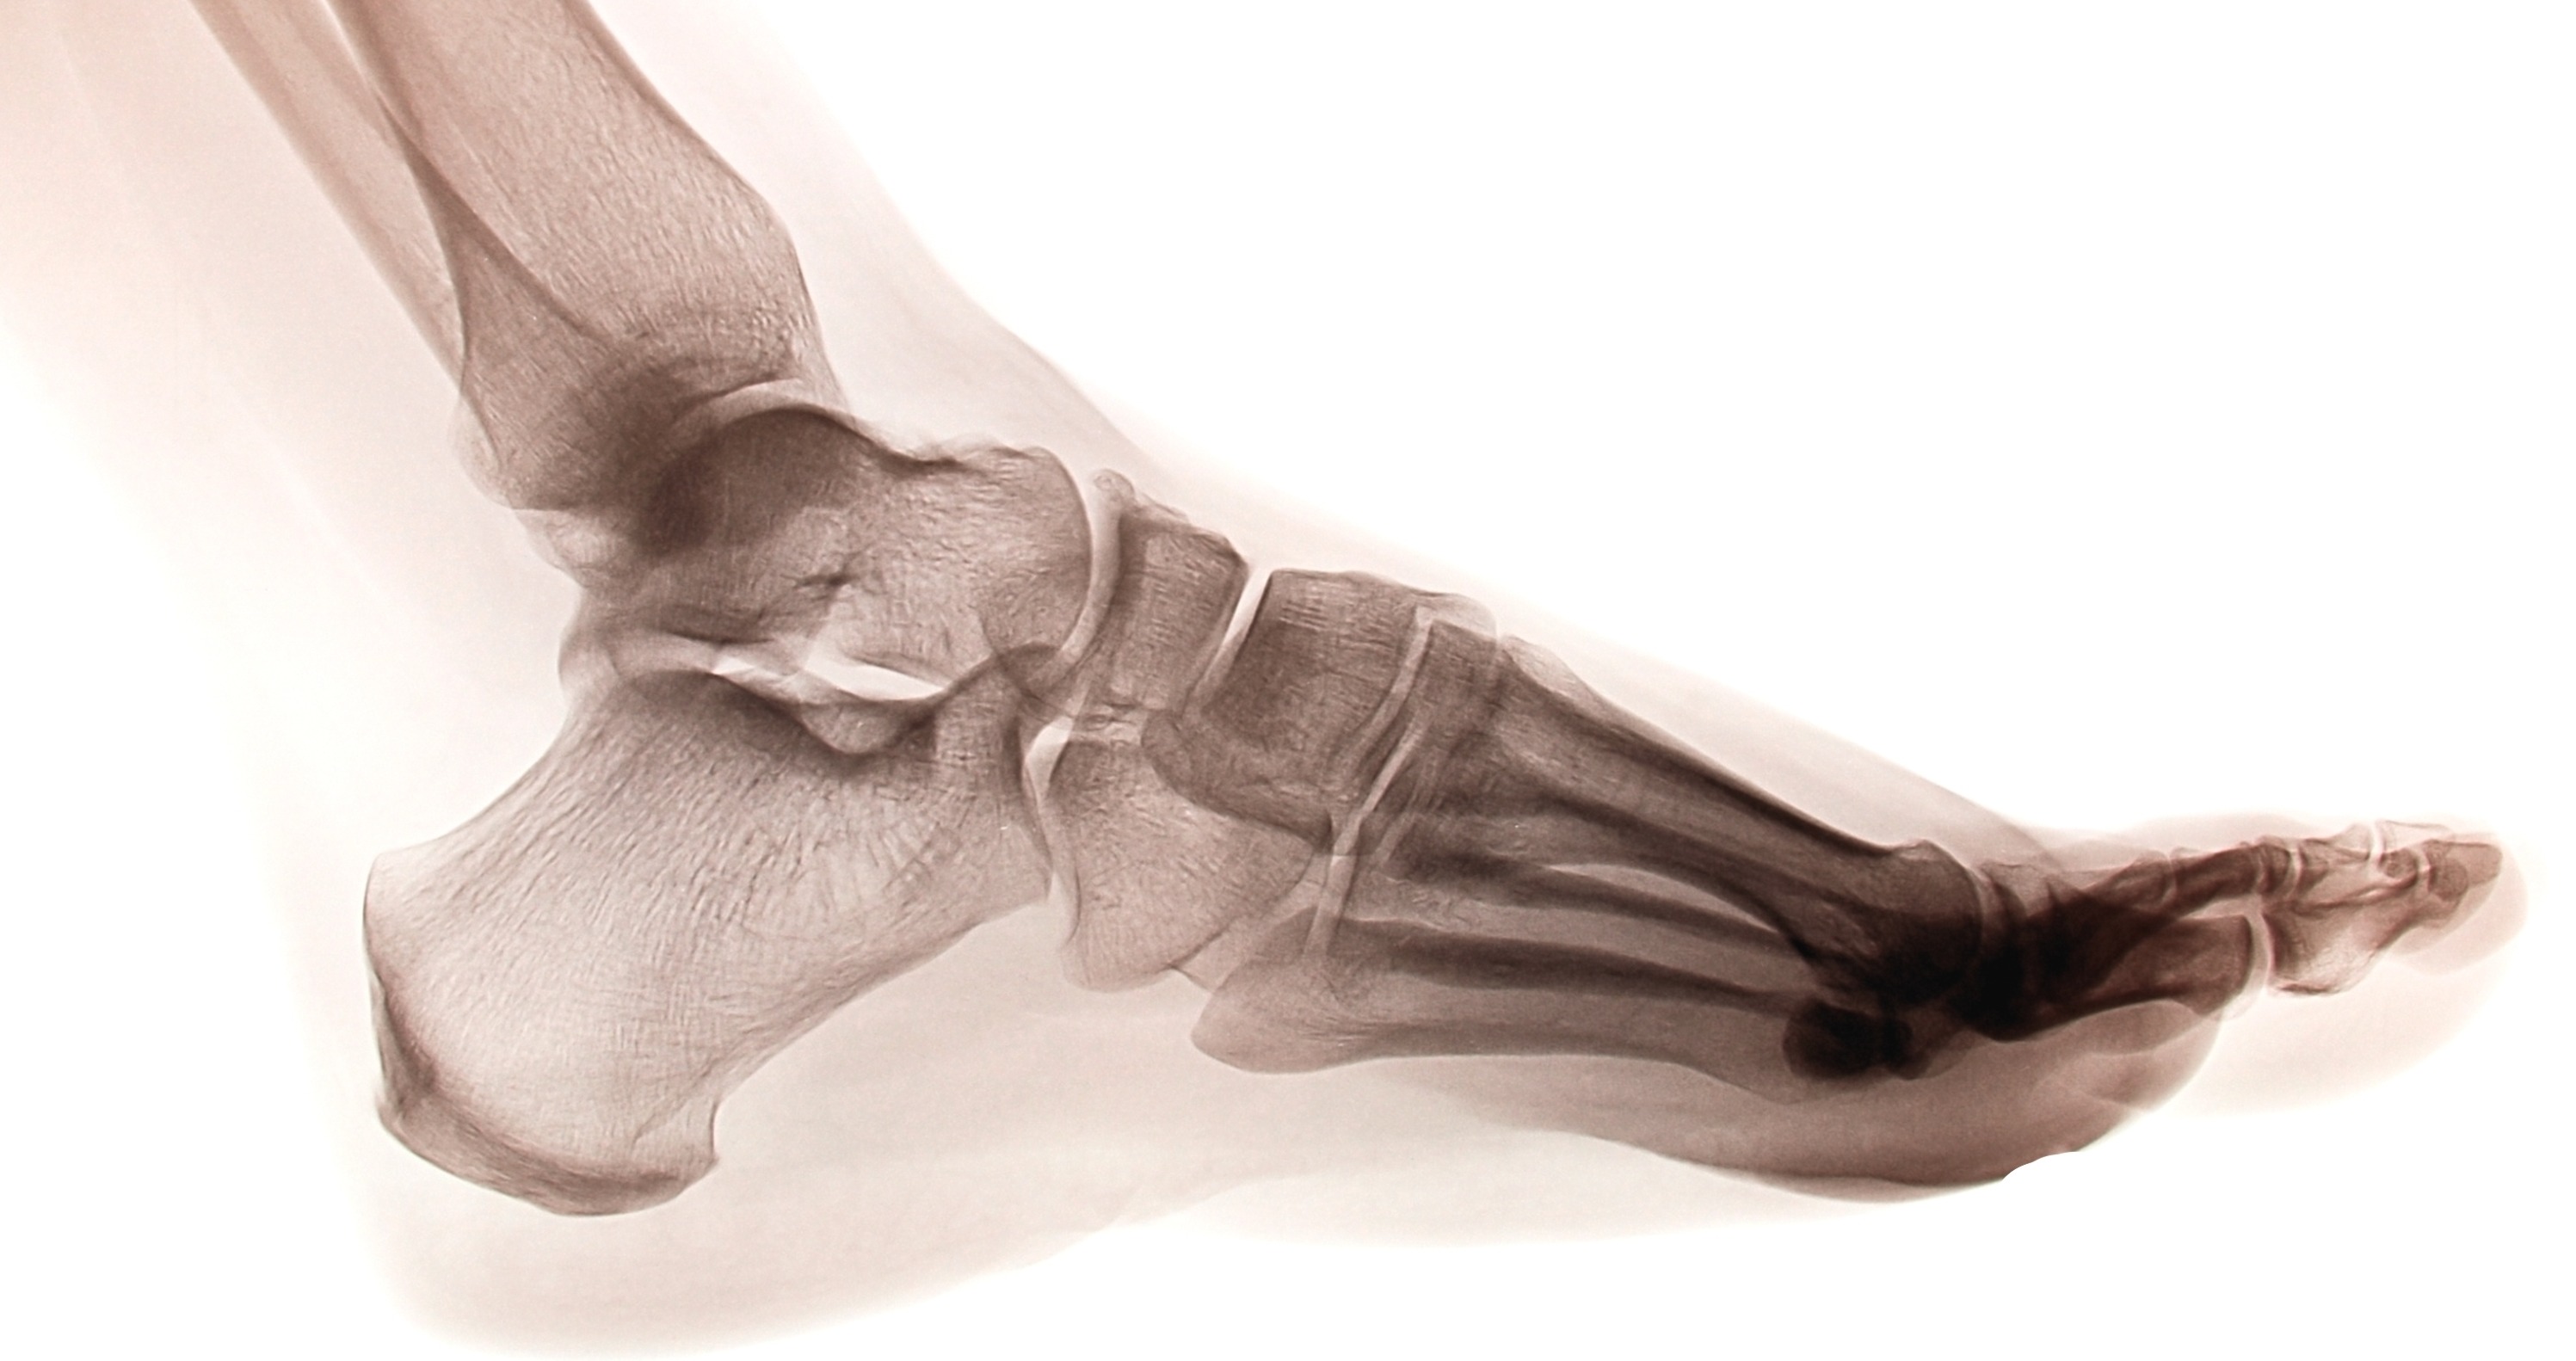

To comprehend the biomechanics of the foot and ankle, you must first understand the intricate structure that enables movement. The foot is divided into three main anatomical regions: the hindfoot, midfoot, and forefoot—each playing a unique role in foot biomechanics.

Hindfoot Biomechanics

The hindfoot, located immediately under the ankle joint, forms the posterior foundation of foot biomechanics. This region consists primarily of two crucial tarsal bones:

• Talus: The primary bone connecting the foot to the lower leg

• Calcaneus: The heel bone that bears initial ground contact forces

The hindfoot's biomechanical function centers around the subtalar joint, which allows for inversion and eversion movements crucial for adapting to uneven surfaces and absorbing impact forces.

Midfoot Biomechanics

The midfoot contains five additional tarsal bones that contribute significantly to the biomechanics of the foot:

• Navicular bone

• Cuboid bone

• Three cuneiform bones (medial, intermediate, and lateral)

The junction between the midfoot and hindfoot, known as Chopart's joint, plays a vital role in foot biomechanics by allowing the foot to adapt its shape during different phases of gait.

Forefoot Biomechanics

The forefoot includes the metatarsals, phalanges, and sesamoid bones. The Lisfranc joint, where the midfoot and forefoot meet, is crucial for push-off mechanics during the propulsive phase of gait.

The complete foot structure encompasses:

• 28 bones working in coordination

• 112 ligaments providing stability

• 33 joints enabling complex movement patterns

• 34 muscles generating and controlling motion

This intricate network demonstrates why foot and ankle biomechanics are so complex and why small dysfunctions can have significant impacts on overall movement quality.